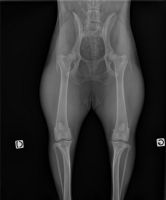

Dépistage officiel de la dysplasie de la hanche et du coude.

radiographie abdominale vétérinairemégaoesophage infini‘Vetfécalome infini‘Vetradiographie dysplasie coxofémorale chien